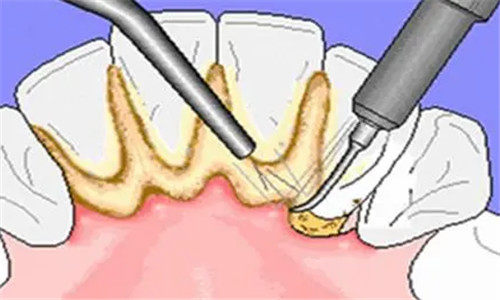

深度洗牙(牙周治疗):价格约800-3000元起

针对牙周炎、牙结石堆积重的或牙龈萎缩的患者,需结合龈下刮治、根面平整等复杂操作,费用较高但结果持久。

深度洗牙:复杂病情拉高费用

深度洗牙需医生使用可靠器械深入牙周袋清理结石,并可能配合局部用药或缝合,对医生技术要求极高。以青岛大学附属医院为例,轻度牙周炎治疗约800元,重度病例(需多次复诊)费用可能突破2000元。